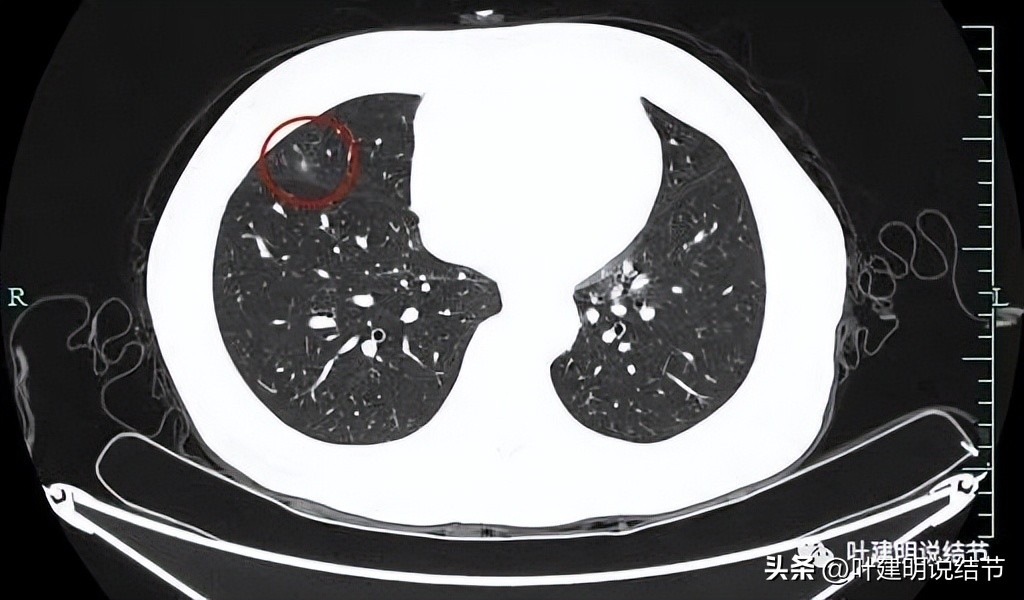

囊壁较薄,但不均匀,有的地方还是显略厚了点的。

似乎见微小血管走向病灶。

微小血管征确实有。

靶重建后发现病灶囊腔型,桔色箭头示进入的血管有异常增粗,而且壁显得毛糙;黄色箭头示空腔;红色箭头示整体轮廓较清;绿色箭头示有磨玻璃成分,虽然密度较低;蓝色箭头示病灶略有胸膜牵拉影响,只是力较弱而已。